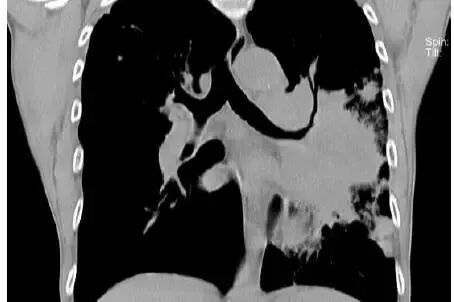

这是什么?

答曰:几乎是鳞癌。

为什么?

因为:鳞癌最容易烂掉!鳞癌天生的烂!乱七八糟的空洞,肿瘤内液化坏死,等等,大部分是鳞癌

肿块+液化坏死 ≈ 鳞癌。

肺门肿块,肿块侵入支气管,鳞癌。假如出现阻塞性肺炎,更支持鳞癌